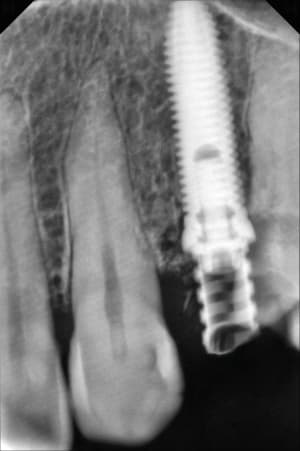

558904719_10163144646272247_6774572045327740986_n.jpg